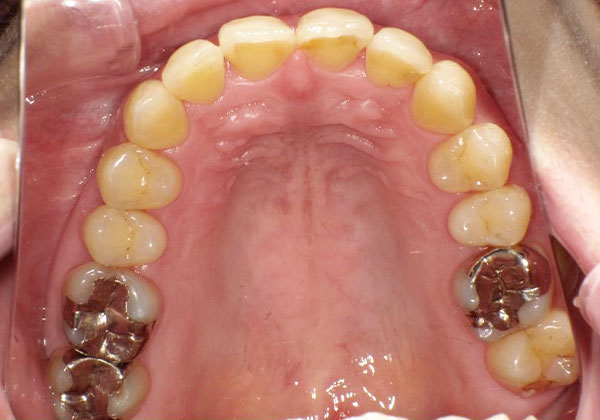

◆マウスピース矯正(50代女性)

(主訴)抜歯をせず歯並びを治したい、矯正中も目立たない方法がよい。

非抜歯で1年弱の治療期間で上下ともに歯列が整った症例です。治療結果だけでなく、費用や治療期間についても想定より安く・短く済み、「治療をもっと早く開始すればよかった」というお声をいただきました。